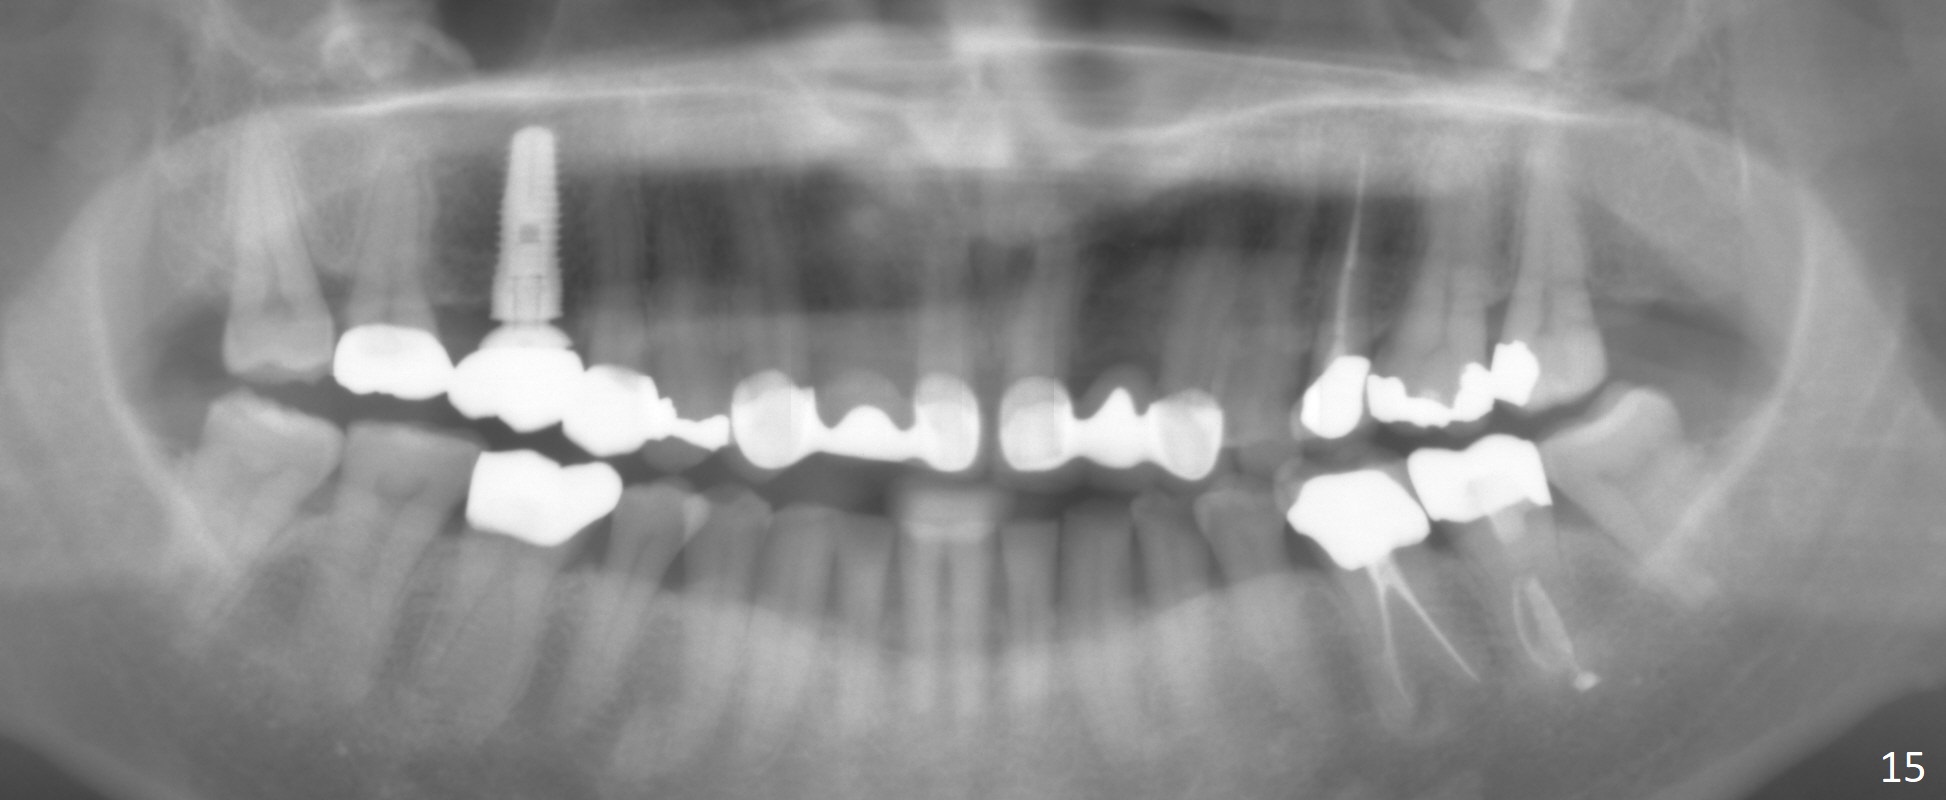

The bone density (Fig.1 white *) at the edentulous area (#3) is lower than that at the dentulous one (black *, 50 year-old man). The buccal plate is also atrophic and concave (Fig.2,3 arrowheads). A series of bone expanders are used to form osteotomy (following 1.6 mm pilot drill) at the depth of 14 mm (Fig.3 E 3.0 mm in diameter). When the last expander (4.3 mm) is removed from the osteotomy, the buccal plate appears to have been moved buccally (Fig.5 arrowheads). A 5.3x14 mm submerged implant (Fig.6 I) is placed with insertion torque >35 Ncm. The buccal plate seems to improve following placement of an 8.2 mm healing abutment and suturing (Fig.7). No bone graft is used. The buccal plate remains normal 12 days postop (Fig.8). It is slightly concave 3 months postop (Fig.9) with minimal bone resorption at the crest (Fig.10 (H: healing abutment),11 (A: cemented abutment). Nine months post cementation (12 months postop), bone resorption at the crest remains minimal (Fig.12) while the buccal plate (Fig.13 *) at #3 remains strong. Bone loss appears not to get worse 22 months post cementation (Fig.14). Soft and hard tissues remain healthy around the implant crown 3 years (Fig.15) and 3.5 years (Fig.16,17) post cementation.

In brief, bone expanders or osteotomes can be used for bone expansion and condensation to improve primary stability of implant placement. No bone graft appears to be needed. The buccal concavity remains minimal 6 years post cementation (Fig.18). In fact he is a bruxer with torus palatinus (Fig.19). The bridge of #9-11 is loose because of subgingival fracture of the abutment of #11 for 2.5 years (Fig.20).